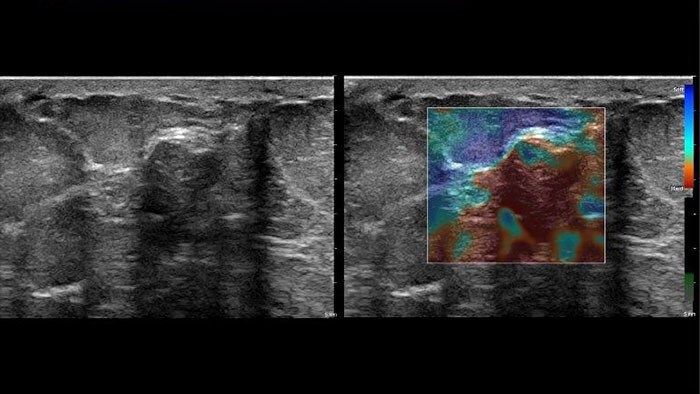

US Q-App Elastography Analysis (EA)* allows you to strain elastography analysis of tissue deformation based on an elastogram. The applications can be used to size compare between two ROIs; results may be appended to patient reports.

US Q-App Elastography Quantification (EQ)* allows you to strain elastography quantification of tissue deformation based on an elastogram. Calculate and display the strain rate and total strain, size compare between two ROIs, and strain ratio; results may be appended to patient reports.